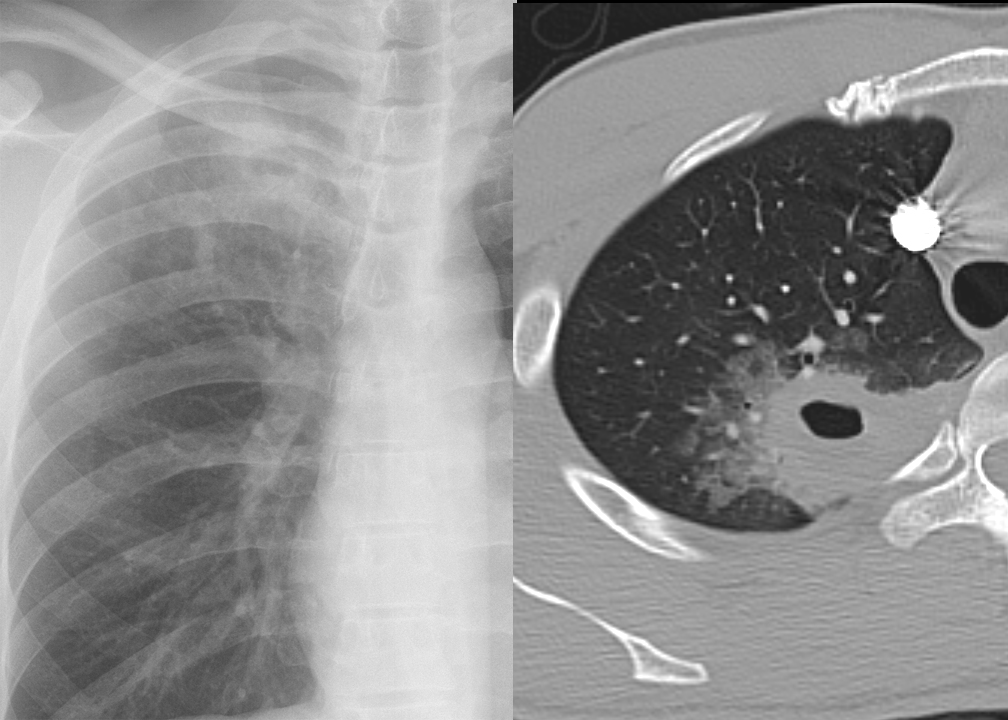

Cavitating pneumonia